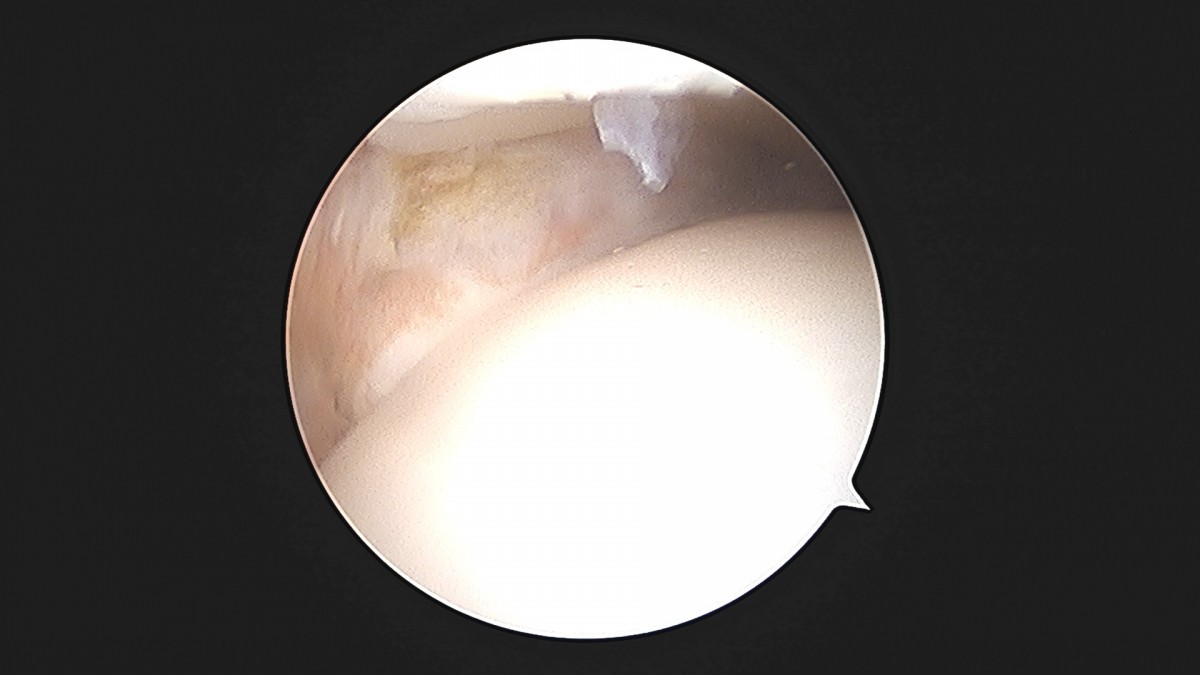

이재상원장님 발목 활액막 절제술 및 인대 봉합술 이승O 환자

작성자 최고관리자 댓글 0건 조회 787회 작성일 25-09-16 15:24